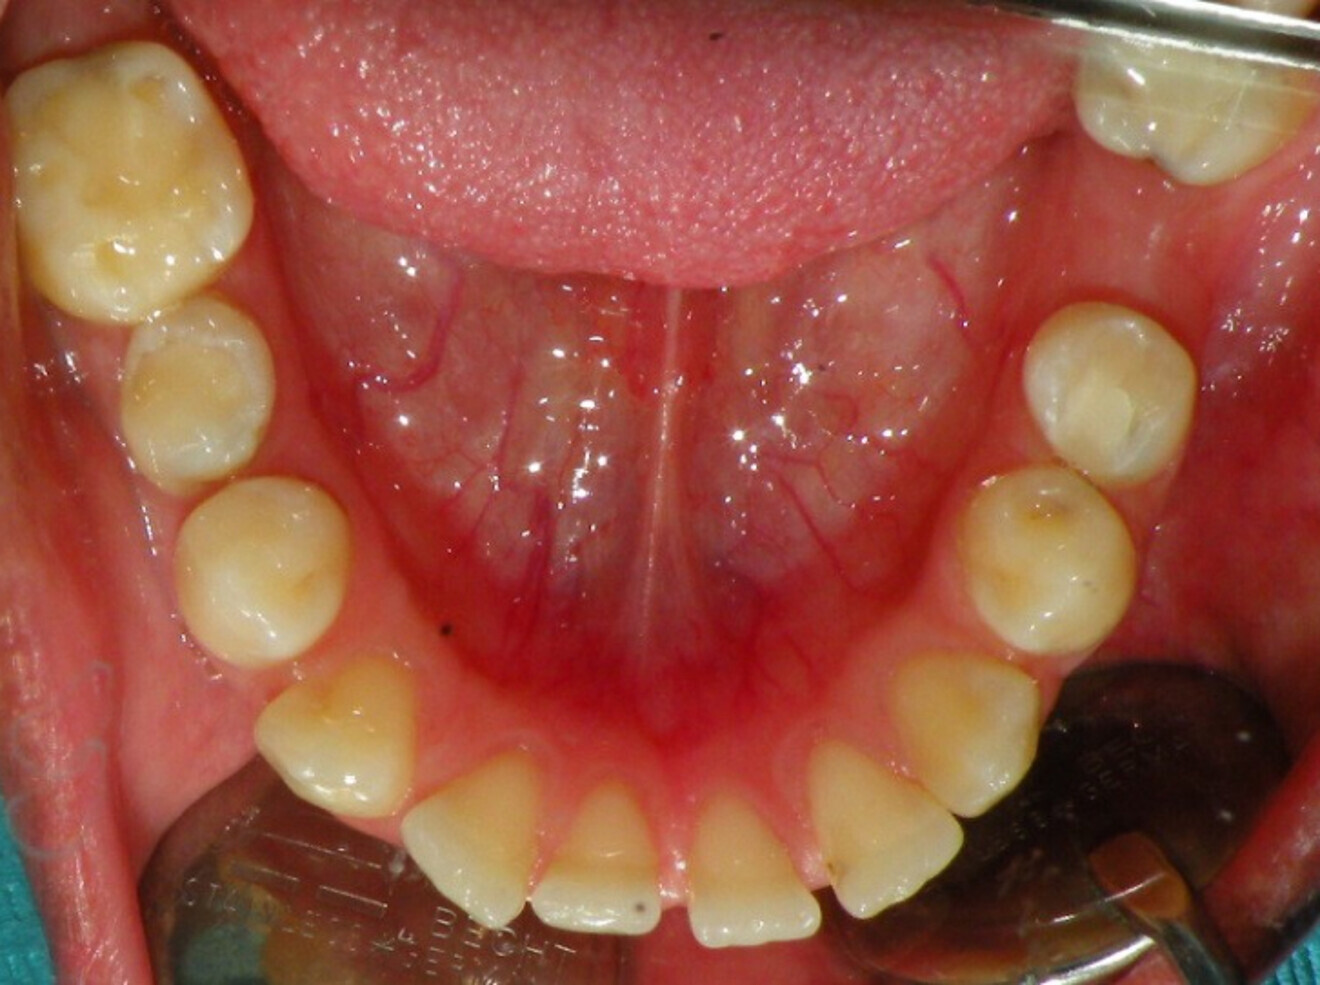

Intra-oral findings:

Class I malocclusion with poli diastemas in both upper and lower arch.

Overbite= 1mm Overjet = 3mm

No molar classification (absence of molars)

Class I canine on right and left side.

Upper midline (mesial to 11) on with face.

Lower midline on with the chin.